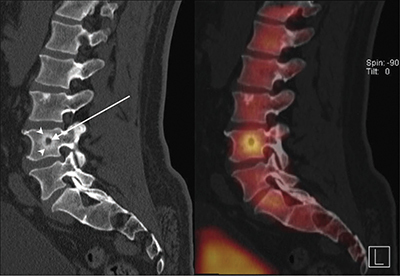

Epithelioid hemangioendothelioma (EHE) is a rare vascular tumor that can originate in various parenchymatous organs, soft tissue, and bone. Extrahepatic involvement is exceedingly rare. In this case, multifocal disease in the spleen and bone was present. Bone lesions showed a target appearance. Splenic lesions showed delayed enhancement of solid components with persistent rim enhancement. A bone biopsy with CAMTA1 staining confirmed the diagnosis. Teaching point: The presence of multifocal bone and splenic lesions can raise suspicion of EHE when other multifocal diseases are excluded.

上皮样血管内皮瘤(EHE)是一种罕见的血管肿瘤,可起源于各种实质性器官、软组织和骨骼。肝外受累极为罕见。在该病例中,脾脏和骨骼出现多灶性病变。骨病变呈靶状。脾脏病变显示实性成分延迟强化,边缘持续强化。经CAMTA1染色的骨活检确诊。教学要点在排除其他多灶性疾病的情况下,出现多灶性骨和脾病变可引起对 EHE 的怀疑。